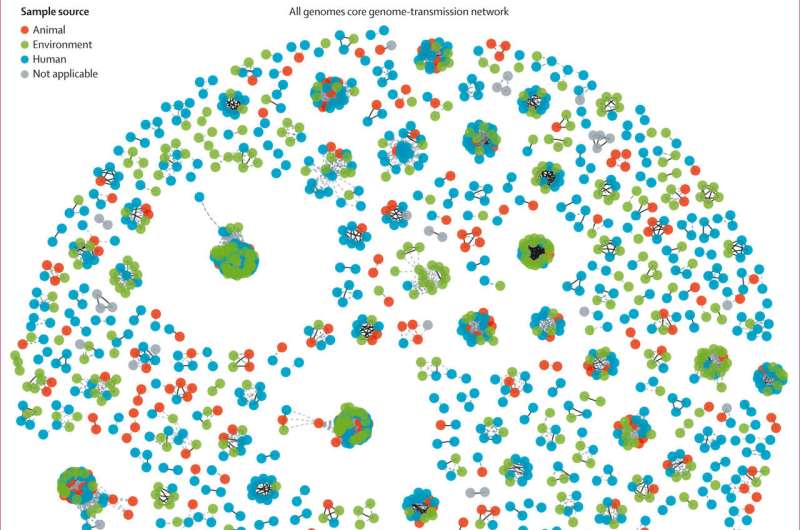

Gene và vi khuẩn kháng kháng sinh có thể di chuyển tự do giữa con người, động vật và môi trường

Thông qua việc phân tích bộ gene của vi khuẩn Escherichia coli (E. coli), các nhà nghiên cứu phát hiện các gene và vi khuẩn kháng kháng sinh có thể di chuyển tự do giữa các vật chủ vi khuẩn và môi trường. Đây là dữ liệu hữu ích cho các biện pháp can thiệp y tế công cộng trong tương lai nhằm giảm thiểu sự lây lan của các bệnh truyền nhiễm kháng kháng sinh, cũng như giúp chúng ta hiểu thêm về cách đối phó với nguy cơ kháng kháng sinh trên toàn cầu.